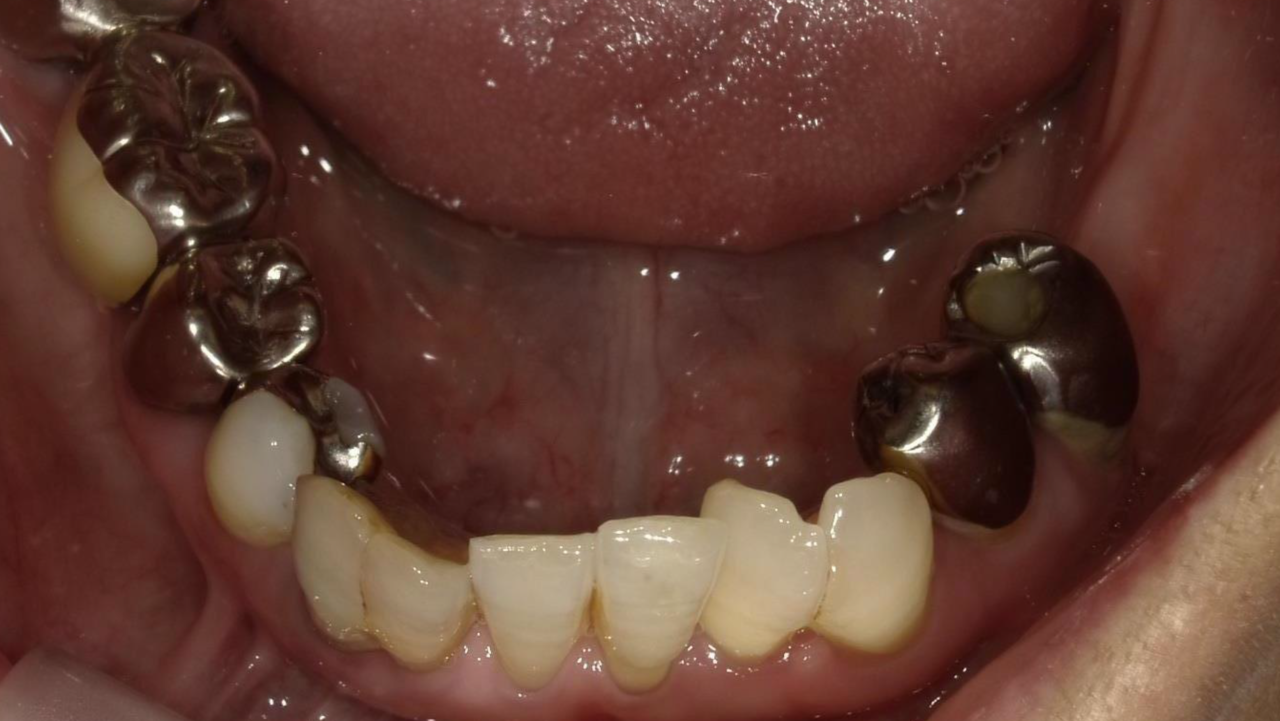

Y・F様 女性 70代

Before

After

以前から左下奥歯がなく硬いものが噛めず、かみ合わせが不安定なため、欠損部にインプラント治療を希望され、治療を開始。治療後、奥歯でしっかり噛めるようになり、食事も美味しく食べれるようになったと満足されていました。

治療期間・回数:7か月、10回

治療の価格:インプラント治療  550,000円 (上部構造含む)

治療のリスクや副作用:手術後に、痛みや腫れ、出血、合併症などを引き起こす可能性があります。噛む感覚がご自身の歯と異なる場合があります。見た目がご自身の歯と異なる場合があります。手術後にメインテナンスを継続しないと、インプラントが脱落するリスクがあります。